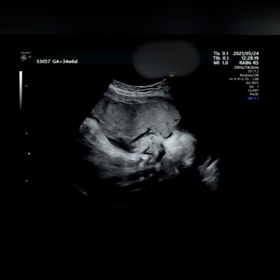

【4人目33w34wの健診】動画あり。初の院長先生